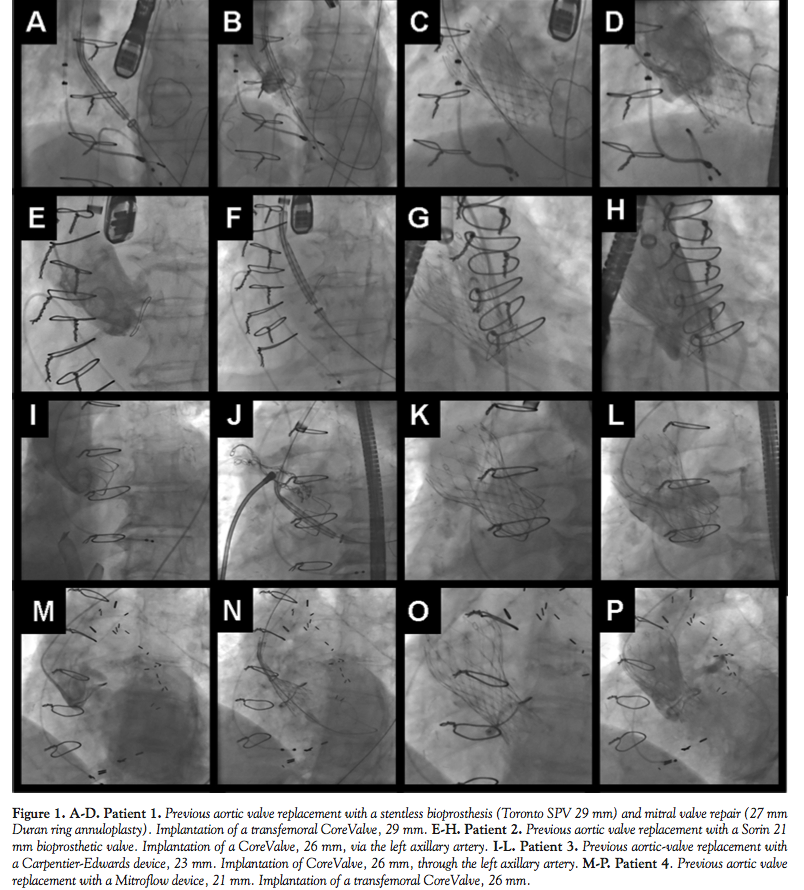

Four procedures were performed with a CoreValve device (2 transfemoral access, 2 transaxillary access) and 2 with an Edwards-SAPIEN device (transapical access). All VIV procedures were technically successful (Figures 1 and 2). None of the patients had vascular problems, stroke, or other major complications. In the aortic procedures, the mean valve gradient decreased from 43 ± 9.3 to 12.3 ± 8.6 mmHg (p < 0.001). Patients were discharged 5.2 ± 1.3 days after the procedure. Thirty-day survival was 100%. There was a significant improvement in patient functional class from before the procedure (0% class I/II, 50% class III, 50% class IV) to after the procedure (66% class I, 33% class II, 0% class III/IV) (p < 0.001).